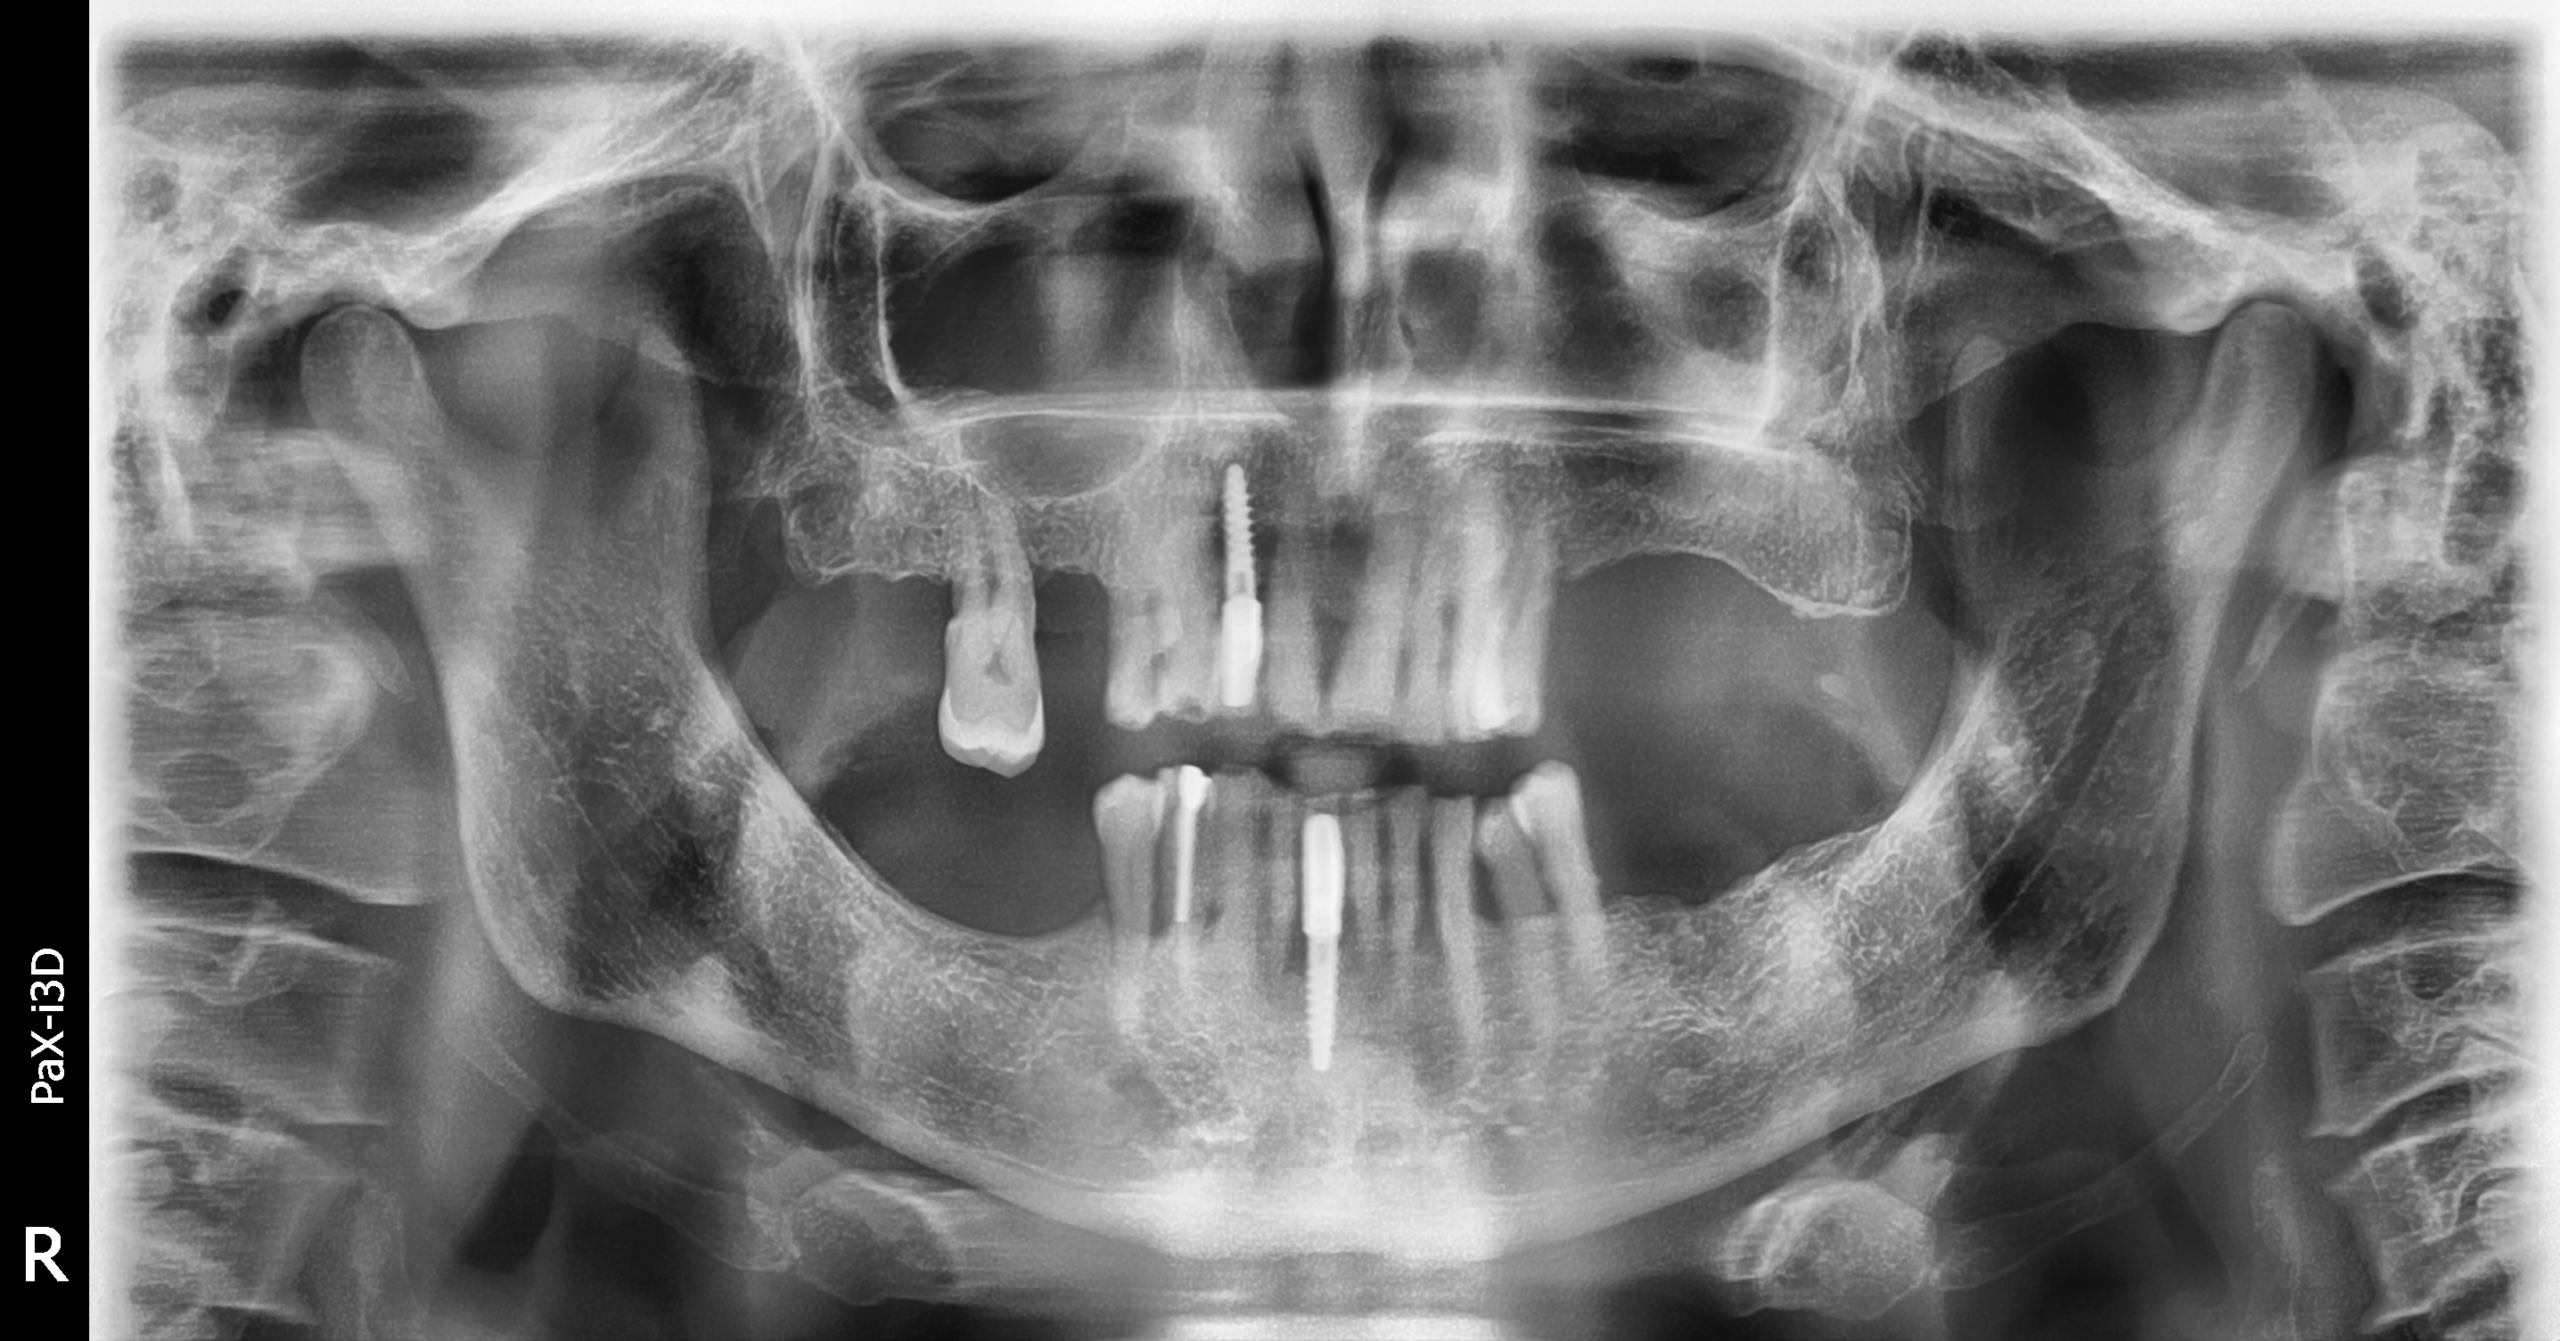

Caso clínico con implantes Radhex monofásicos, por el Dr. Juan José Soleri

Planificación quirúrgica estratégica para una paciente con sector II atrófico y seno maxilar III-IV.

No admitía elevación sinusal, ni injertos. Rehabilitación con Radhex Implants.

Exodoncia atraumática de 2.4 y colocación de implante basal SLD-bm, en zona 2.5 colocación de implante SLD-c inclinado medialmente anclado en la encrucijada ósea.